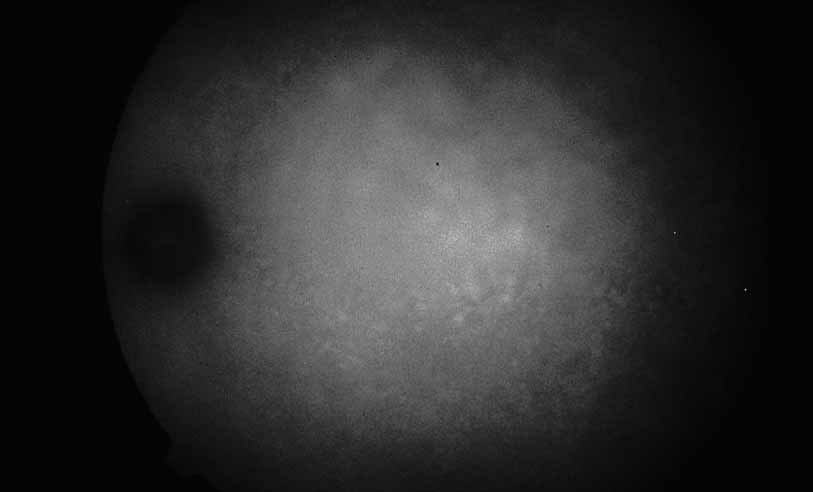

A third instance in which fluorescein angiography concentrating on the optic nerve may be helpful is in eyes with vascular engorgement of the optic nerve, especially with media opacities. Fluorescein angiography may help the clinician distinguish abnormally leaking capillaries from neovascularization. In acute multifocal hemorrhagic retinal vasculitis, optic nerve involvement is common in the early stages of the disease, 47 with optic nerve disc neovascularization seen later (see Figs. 10, 11, 12, and 13). Another fluorescein angiographic clue to the distinction between optic disc vessel engorgement and true neovascularization is the presence of associated large zones of retinal capillary nonperfusion such as those seen in sarcoidosis (see Figs. 14 and 15),34–40 acute multifocal hemorrhagic retinal vasculitis (see Figs. 10 and 11),47 or Eale disease (see Figs. 16 and 17).48–52

Fig. 10 Acute multifocal hemorrhagic retinal vasculitis. A middle-aged man presented with the picture of multiple branch vein obstructions and low-grade intraocular inflammation.